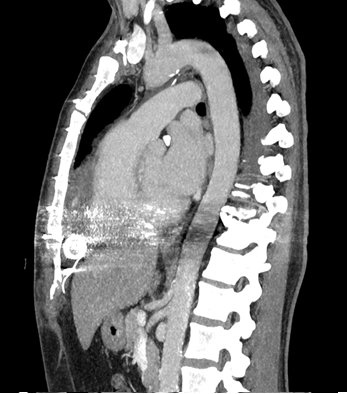

Figure 2

Figure 2: Complete removal of the descending thoracic aortic thrombus after medical treatment

Although very rarely seen, Harlequin syndrome can occur in patients undergoing ECMELLA treatment. Diagnosis can be difficult as symptoms are not specific. In this special population, medical/conservative therapy looks to be a good and less invasive treatment. Although only one third of DTAT are completely resolved through medical therapy [3], it was successful in our case. As systemic embolization can occur at any time, early treatment can benefit morbidity and increase survival.